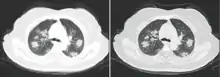

Chest CT scans may be helpful to diagnose COVID-19 in individuals with a high clinical suspicion of infection but are not recommended for routine screening.[89][121] Bilateral multilobar ground-glass opacities with a peripheral, asymmetric, and posterior distribution are common in early infection.[89][122] Subpleural dominance, crazy paving (lobular septal thickening with variable alveolar filling), and consolidation may appear as the disease progresses.[89][123] Characteristic imaging features on chest radiographs and computed tomography (CT) of people who are symptomatic include asymmetric peripheral ground-glass opacities without pleural effusions.[124]

Many groups have created COVID-19 datasets that include imagery such as the Italian Radiological Society which has compiled an international online database of imaging findings for confirmed cases.[125] Due to overlap with other infections such as adenovirus, imaging without confirmation by rRT-PCR is of limited specificity in identifying COVID-19.[124] A large study in China compared chest CT results to PCR and demonstrated that though imaging is less specific for the infection, it is faster and more sensitive.[88]